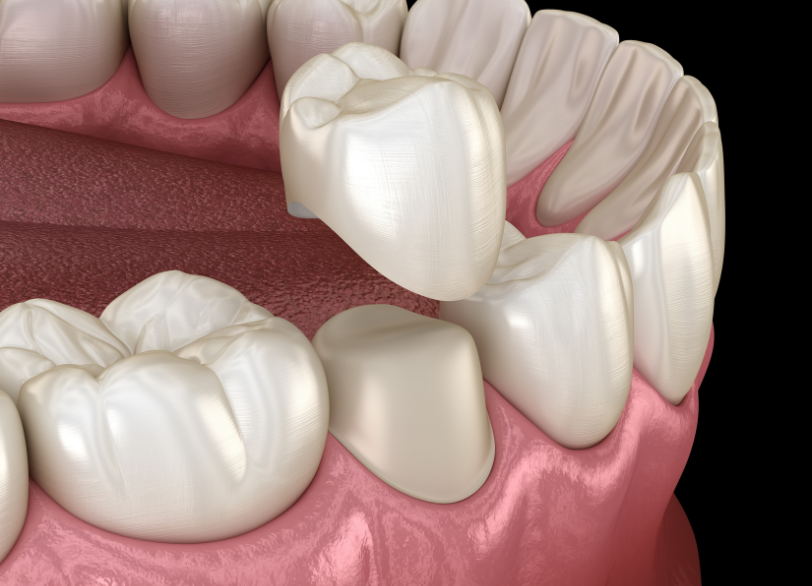

Step 7. 被せ物の装着

型取りを行い、精度の高い被せ物(クラウン)を製作して装着します。

これで噛む機能が回復し、治療完了です。

被せ物の精度が大切

根管治療が成功しても、その上に被せる「被せ物(クラウン)」の精度が悪ければ、意味がありません。

被せ物と歯の間に隙間や段差があると、そこから再び細菌が侵入し、治療したはずの根の先で炎症が再発してしまいます(コロナルリーケージ)。

当院では、適合精度の高い被せ物を作製することにこだわっています。

特に、セラミックやジルコニアといった素材は、変形が少なく、歯と化学的に接着するため、隙間ができにくく、二次虫歯のリスクを大幅に下げることができます。